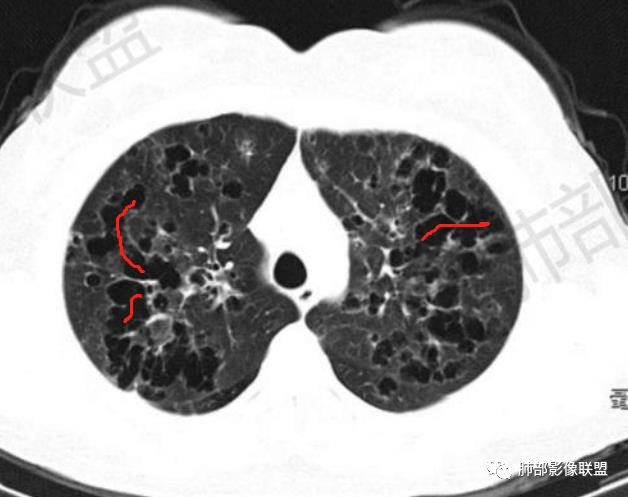

晨读:双肺多发大小不等囊腔影,部分囊有融合,形态不规则,部分壁偏薄,部分囊壁偏厚,囊壁可见结节?血管?右肺上叶及左肺下叶可见条状高密度影,双侧胸膜结节样增厚,临床年轻女性,考虑LAM,鉴别LIP

晨读,青年女性,双肺及胸膜下多发大小不等囊腔,大部分呈薄壁,部分囊壁略厚,边缘毛糙,部分囊腔有融合,双肺内散在条状高密度影,考虑LAM

影像:双肺散在囊性病变,不规则,壁厚,部分见结节

晨读:女,31,间断咳嗽、咳痰9月。卵巢交界性囊腺瘤术后。胸部CT:双肺多发大小不等薄壁囊腔影,部分融合,形态不规则,个别囊壁偏厚。右肺上叶及左肺下叶纤维索条影。左下叶不规则囊腔影,壁不均匀增厚,周围不规则实性成分加GGO,放射性毛刺,胸膜牵拉。考虑:囊腔型Ca?转移?鉴别PLCH,Lam,LIp,BHD,CF,CPAM等,听大咖解析。

胸部CT:两肺多发囊腔,中上肺受累为主,囊腔形态不规则(囊有点丑),分叶状,囊壁厚薄不均,大部分囊壁薄。尚有一些结节影。

4.PLCH:常见于吸烟青年男性,囊腔形态不规则,呈分支状,囊壁厚薄不均,双侧肋膈角常不受累。

晨读囊不规则,分叶,存在PLCH可能,但为不吸烟女性,可能性下降。

5.囊腔型肺转移瘤:常见于头颈部的鳞状上皮癌、胃肠道的腺癌、女性生殖系统肿瘤、肺外肉瘤的转移。

晨读病例有妇科肿瘤手术史,肺内病变转移瘤可能性大(而且一般盆腔肿瘤手术前基本都会完善胸部X检查,能够顺利完成手术估计手术时肺内无明显病灶),但肺囊肿有较明显的融合,这在转移瘤中较少见。综合上述考虑囊腔型肺转移瘤,鉴别PLCH。